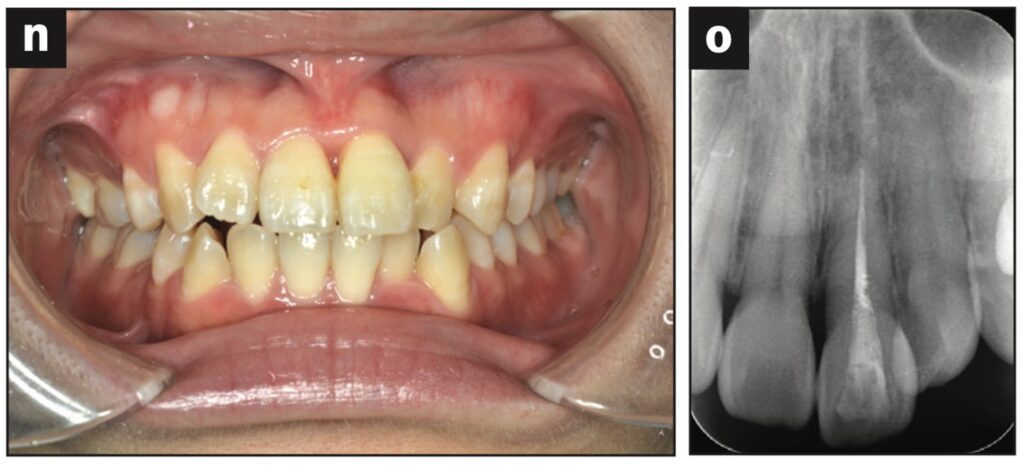

Bệnh nhân nữ 42 tuổi bị ngã khiến răng cửa giữa hàm trên bên trái bị lệch về phía vòm miệng. Đường gãy xương ổ răng ở phía khẩu cái được thấy trên CBCT.

Răng được nắn chỉnh và cố định bằng composite quang trùng hợp rồi lấy dấu. Hai tiếng sau, bệnh nhân quay lại và nhận khay duy trì. Bệnh nhân được hướng dẫn đeo khay duy trì cả ngày trừ khi đánh răng.

Các thử nghiệm tủy được thực hiện sau 7 và 28 ngày. Đánh giá độ lung lay răng, gõ và sờ, thử tủy EPT và chụp X quang được thực hiện sau 28 ngày.

Sau 28 ngày theo dõi, răng hơi lung lay và không đáp ứng với thử tủy EPT. Sau 2 tháng theo dõi, răng không bị đổi màu, không lung lay, âm tính với EPT và hơi nhạy cảm khi gõ. Không có tổn thương quanh chóp trên X quang và không có lỗ dò. Sau 3 tháng theo dõi, răng đã đáp ứng với EPT (9/10) và có cảm giác đau nhẹ khi gõ.

Sau 4 tháng theo dõi, răng đã phản ứng với EPT (9/10) và không còn nhạy cảm với gõ.